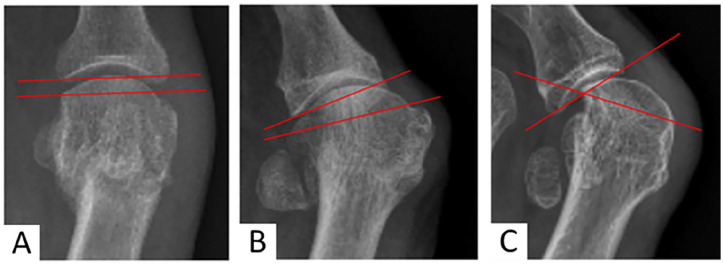

Methods: This retrospective study analyzed 116 feet that underwent percutaneous distal metatarsal transverse osteotomy with lateral soft tissue release and provisional Kirschner wire fixation, with a mean follow-up of 27.1 months, limited to severe cases (hallux valgus angle [HVA] > 40 degrees). Radiologic assessments included preoperative and postoperative measurements of HVA, intermetatarsal angle (IMA), distal metatarsal articular angle, sesamoid position, first metatarsophalangeal (MTPI) joint congruency, metatarsal length, and sagittal position. Clinical evaluations used the AOFAS scale, documenting the recurrence rate, the nature of complications, reoperations, and the association between them. Patient satisfaction was assessed through self-reported evaluations.